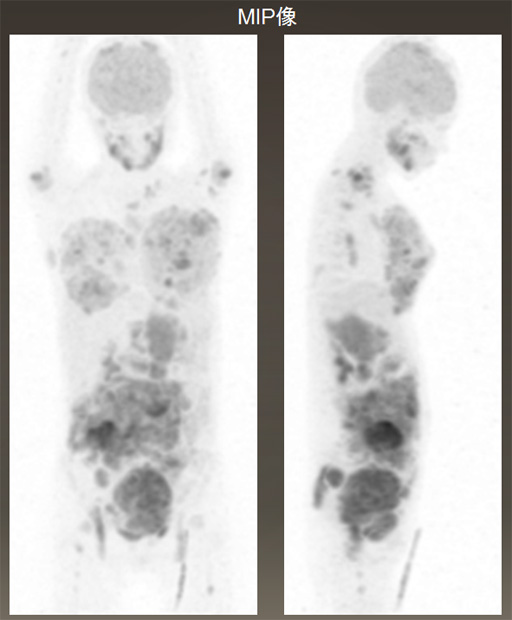

FDG-PET

- 両側乳房、両側卵巣、全身の骨、リンパ節、小腸or腸間膜リンパ節にFDG集積あり。